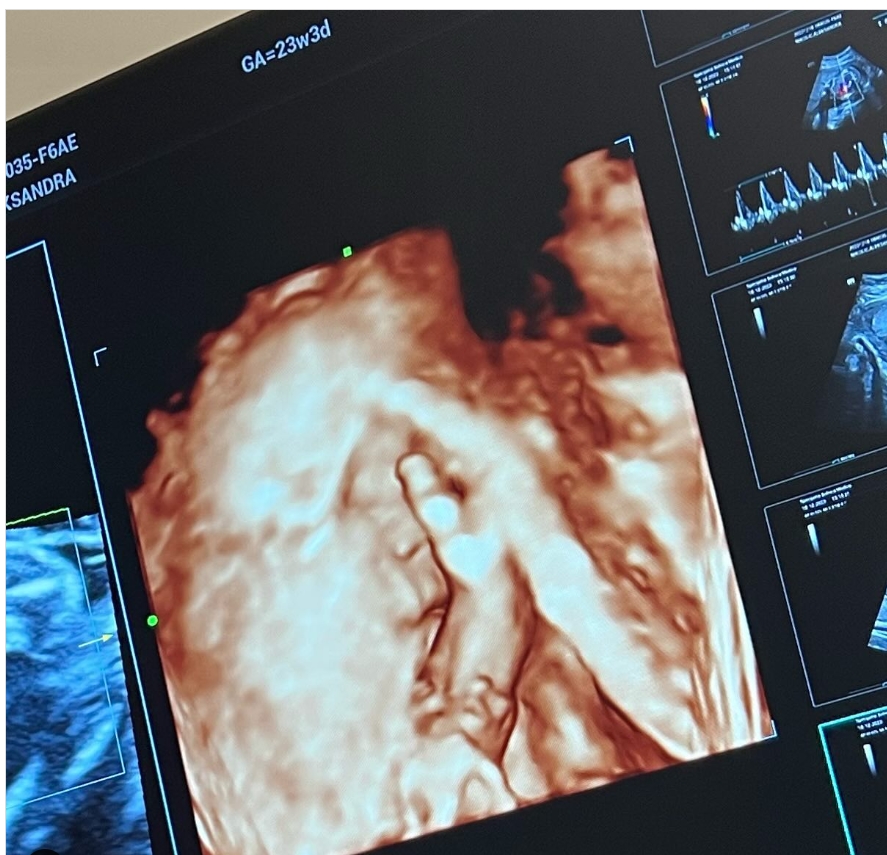

Sada je Aleksandra podelila fotografiju svoje devojčice, a njen opis raznežio je brojne fanove i pratioce na Instagramu, koji su čestitali budućim roditeljima:

– Mala neće da se slika. Ostavite me na miru da spavam! Lepotice naša mala, jedva čekam da se upoznamo…Ne mogu da vam opišem koju sam sreću osetila svaki put kada sam bila na ultrazvuku.Danas sam videla njena stopala kojima stalno šutira mamu,mali prćasti nosić,male rukice,usta…Mislim da neću moći da zaspim od sreće ! – napisala je Aleksandra.